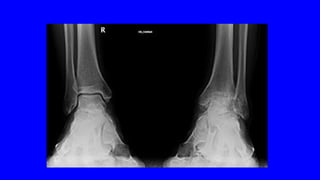

DOLOR CRÓNICO

OSTEOARTICULAR

DOLOR NOCIEPTIVO SOMÁTICO

•ES EL MÁS FRECUENTE

LA ARTROSIS